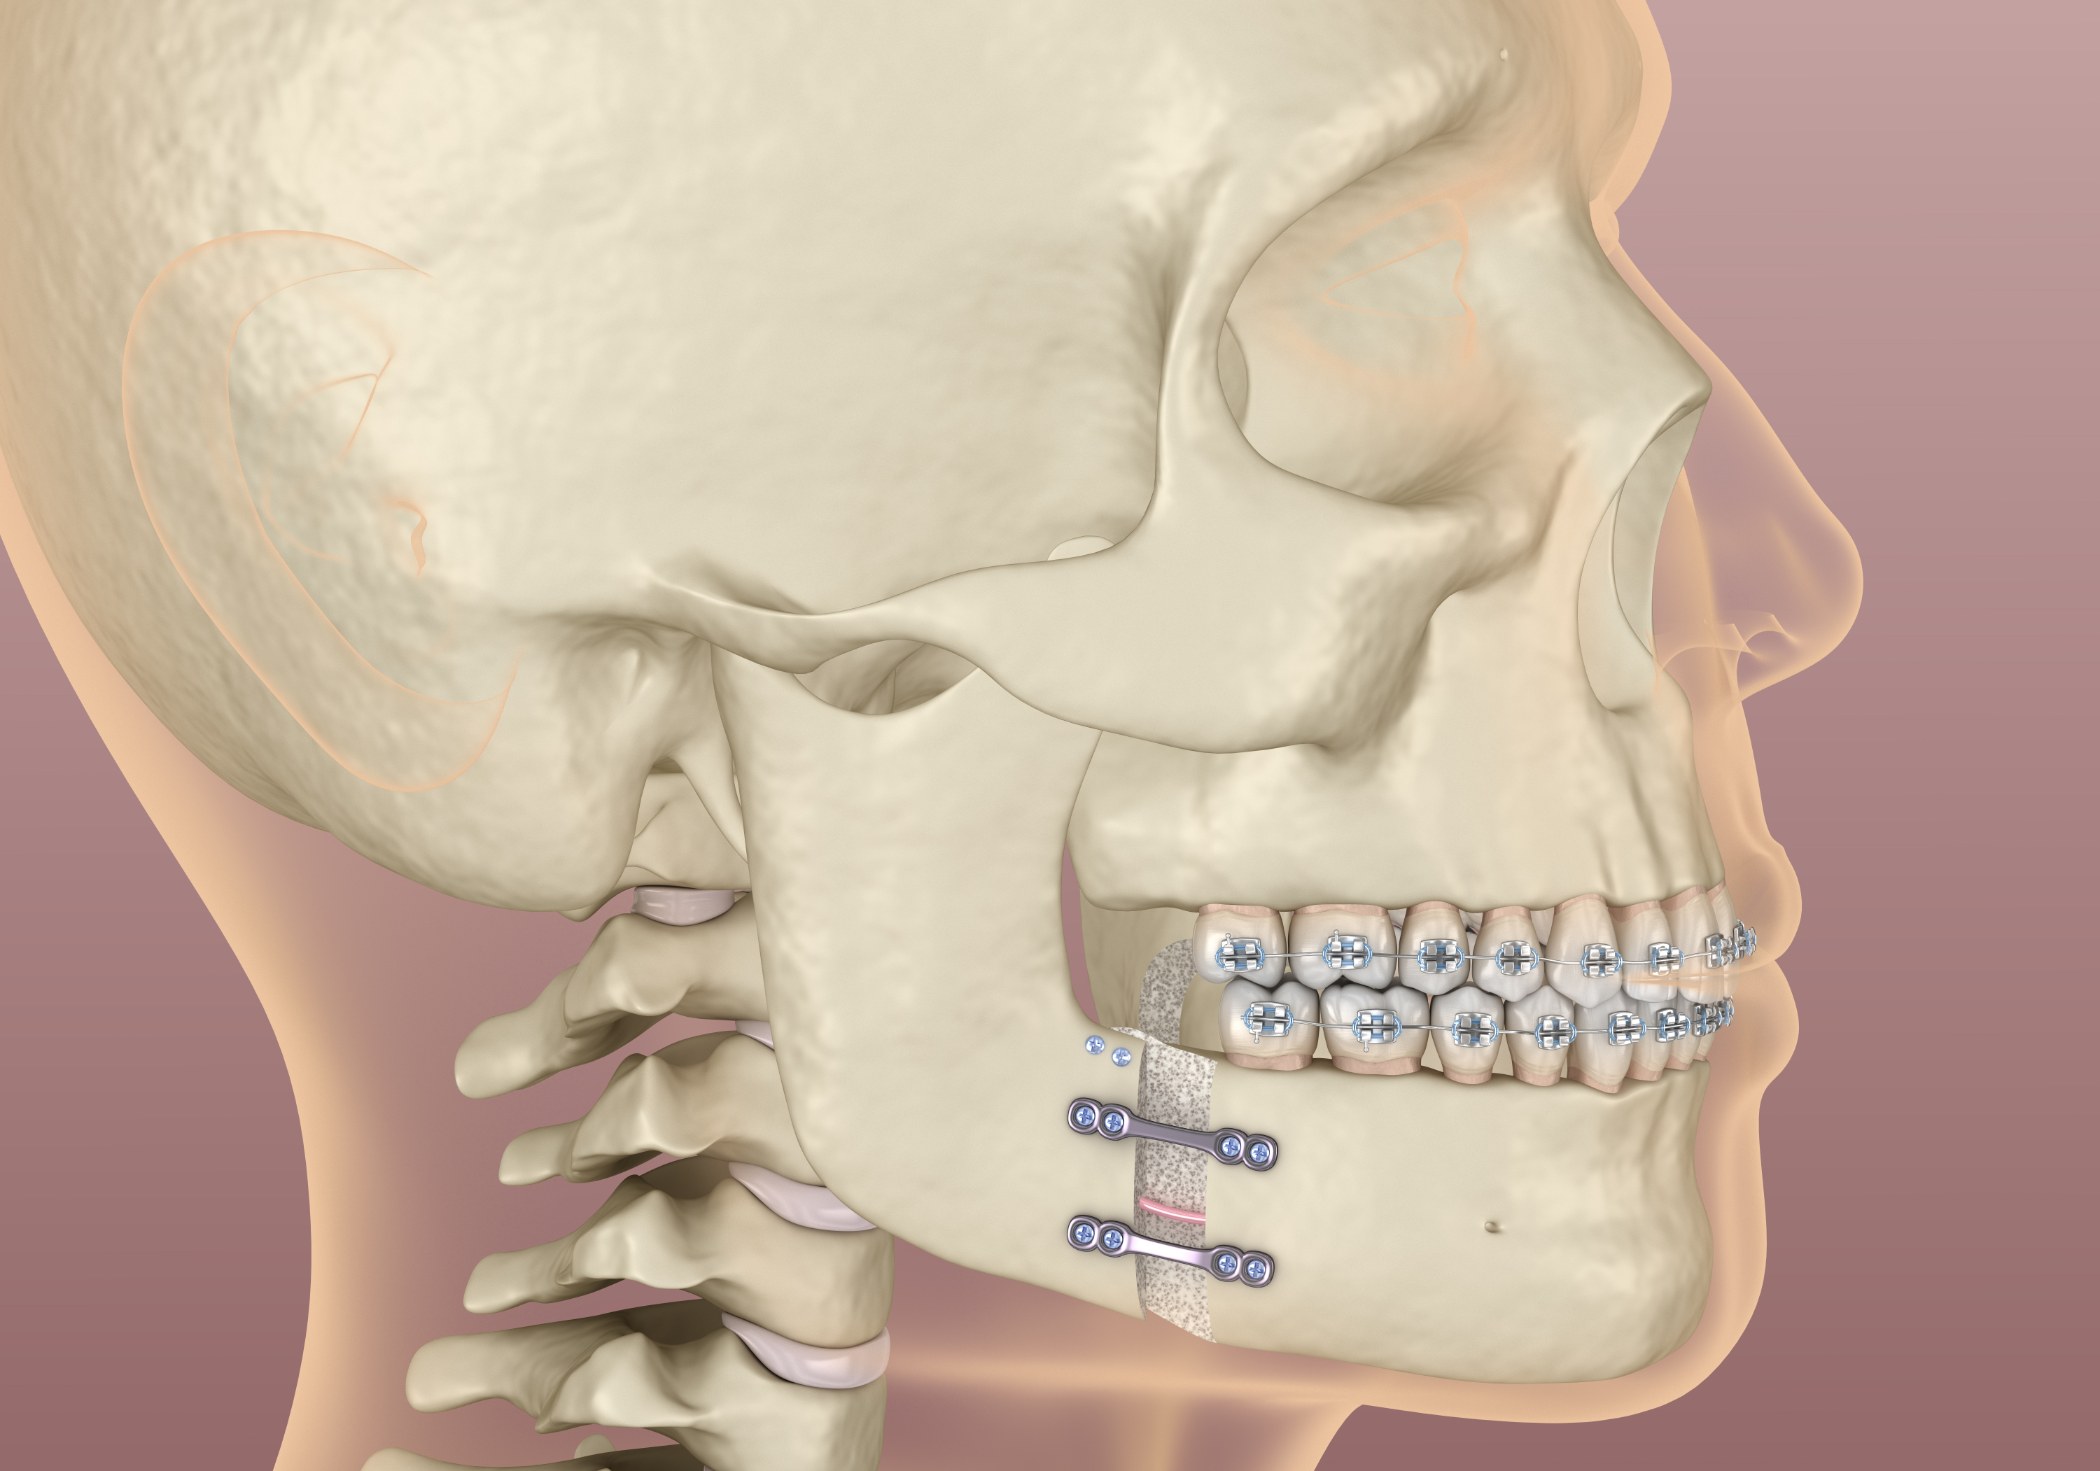

والفكین على موقع الكسر وشدتھ. في حالة حدوث كسر في الفك العلوي أو السفلي ، یمكن تثبیت الأقواس المعدنیة على

الأسنان ، ویمكن استخدام الأربطة المطاطیة أو الأسلاك لتثبیت الفكین معا. في حالة المرضى الذین لدیھم أسنان قلیلة أو

معدومة ، قد تكون ھناك حاجة إلى أطقم الأسنان أو الجبائر المصممة خصیصا لمحاذاة الكسر وتأمینھ. مبادئ علاج كسور

The repositioning technique Oral and Maxillofacial Surgeons uses depends upon the location and severity of the fracture. In the case of a fracture in the upper or lower jaw, metal braces may be fastened to the teeth, and rubber bands or wires can be used to hold the jaws together. In the case of patients with few or no teeth, dentures or specially constructed splints may be required to align and secure the fracture. The principles for treating facial fractures are the same as for a broken arm or leg. Maxillofacial procedures that you can do with Globalmedi